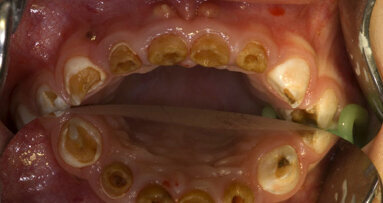

Inzwischen ist bekannt, dass vorübergehende Bakteriämien beim Menschen nach dem Zähneputzen und nach Anwendung von Zahnseide entstehen können. Zunehmend wird in der Literatur auch über einen möglichen pathogenetischen Zusammenhang zwischen latenten chronischen Entzündungen und Störungen des Fettstoffwechsels bzw. Herz-Kreislauf- Erkrankungen berichtet. So gilt inzwischen die Zahnfleischtasche als eine wichtige bakterielle Eintrittspforte anaerober Bakterien bzw. verschiedener lokaler Zytokine in das Herz-Kreislauf-System. Für die destruktiven Prozesse an den parodontalen Geweben und am alveolären Knochen sind u. a. Agregatibacter actinomycetemcomitans und Porphyromonas gingivalis verantwortlich (Abb. 1a–b). Es gibt aber zunehmend auch Hinweise, dass gramnegative orale Bakterien in der Ätiologie der Arteriosklerose eine Rolle spielen. Zambon et al. wiesen Porphyromonas gingivalis in arteriosklerotischen Plaques bei Patienten mit koronarer Herzkrankheit nach. Genco et al. sprechen von einem erhöhten Risiko für Myokard - infarkte beim Nachweis von Porphy - romonas gingivalis und Tannerella forsythia in der Zahnfleischtasche.